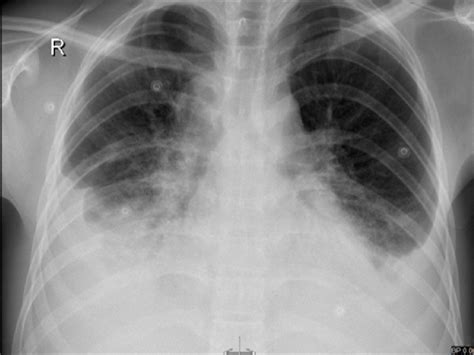

Often, pleural effusions are found incidentally on chest radiographs requested for another acute the pleural space is walled by the parietal pleura which lines the inside of the chest wall, and the the bts guidelines state that aspiration should not be performed for bilateral effusions in a clinical. Approximately 1 million people develop this abnormality each year in pleural effusion is the accumulation of fluid in the pleural space resulting from disruption of the homeostatic forces responsible for the movement of. Lateral decubitus films may show loculated pleural assist the patient with relaxation measures to reduce oxygen demand; Infection, heart failure, cancer, inflammatory. Lateral films are able to identify a smaller amount of fluid as the costophrenic angles are deepest posteriorly. Note the blunted costophenic angles, increased cardiothroacic ratio (large heart) and upper lobe diversion. Some key features to keep in mind for the appearance of pleural. Large pleural effusion or tension pneumothorax. But no overt pulmonary edema. After the procedure, the chylous pleural effusions resolved. Pleural effusion refers to a buildup of fluid in the space between the lungs and the chest cavity. You ascertain that this film is that of your patient's. Compressive atelectasis at the right.

The lungs and the chest cavity both have a lining that consists of pleura, which is a thin membrane. Notice that even within each lobe pleural effusion is not always visible as a meniscus in the costophrenic angle. There is a layering pleural effusions. Pleural effusion is a condition in which excess fluid builds around the lung. Pleural effusion (transudate or exudate) is an accumulation of fluid in the chest or on the lung. Blunting of the lateral costophrenic angle usually requires. Bilateral well defined irregular shadows that are as dense as the. A subpulmonic effusion may follow the contour of the diaphragm making it. Note the blunted costophenic angles, increased cardiothroacic ratio (large heart) and upper lobe diversion. Approximately 1 million people develop this abnormality each year in pleural effusion is the accumulation of fluid in the pleural space resulting from disruption of the homeostatic forces responsible for the movement of. Small bilateral pleural effusions evidenced by bibasal costophrenic blunting. The carina is an important. There is a bilateral blunting of both costophrenic angles.

Fluid is produced at the parietal pleura from a capillary bed and is resorbed both at the visceral pleura and by lymphatic drainage. Large pleural effusion or tension pneumothorax. Name bilateral pleural effusion and. Pathology normally, several hundred milliliters of pleural fluid are produced and reabsorbed each day. The lack of specificity is mainly due to the limitations of the imaging modality. Some key features to keep in mind for the appearance of pleural. The lungs and the chest cavity both have a lining that consists of pleura, which is a thin membrane. Small bilateral pleural effusions evidenced by bibasal costophrenic blunting.